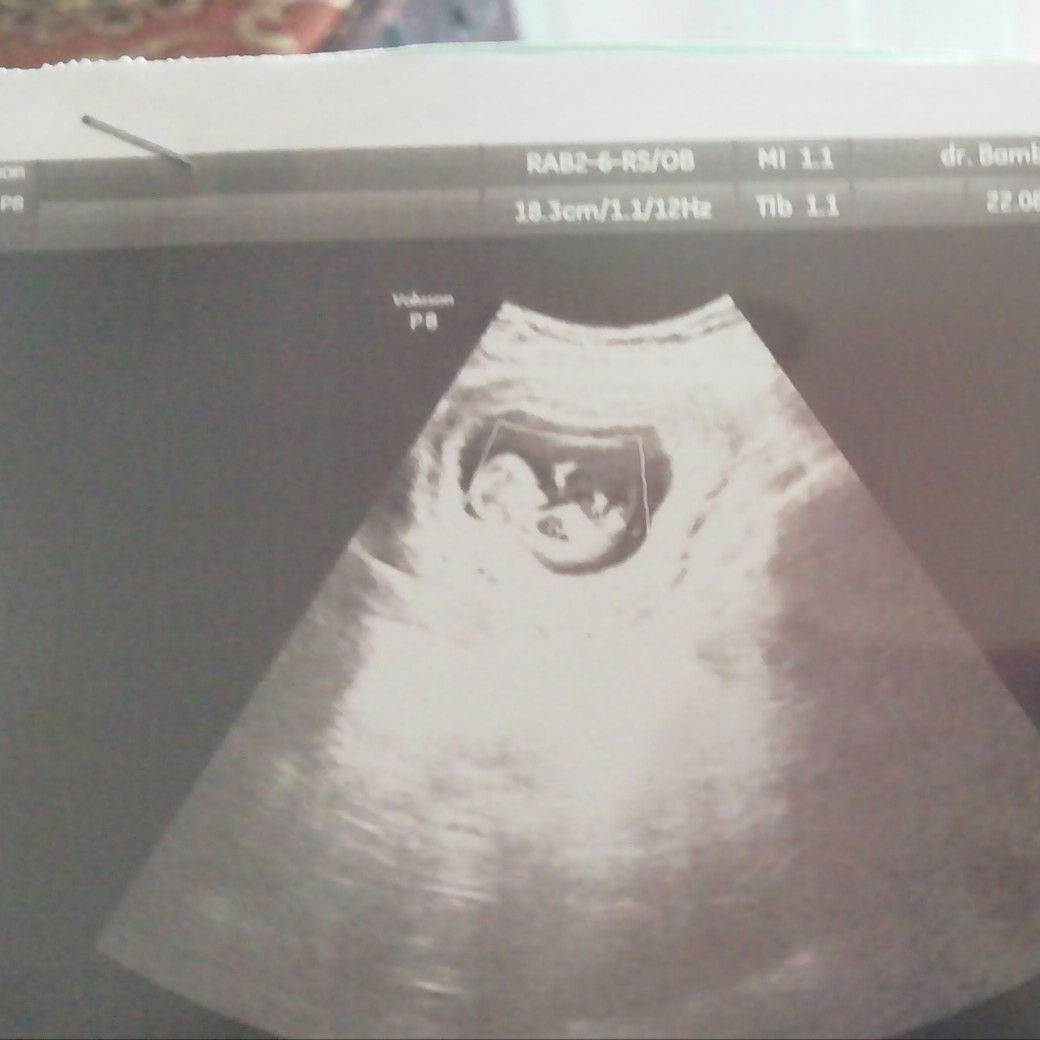

Hamil 10 Minggu

Hasil usg hri ini, alhamdulillah sehat???